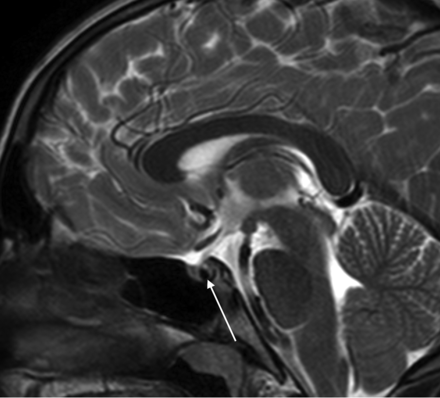

On the basis of the results of our study, we advocate for use of a rapid noncontrast pituitary MR imaging protocol for pediatric patients presenting with GHD, CPP, or SS. This protocol includes coronal and sagittal TSE T1-weighted multipoint Dixon (mDixon) and sagittal T2-weighted thin-section images of the sella, axial T2WI or FLAIR of the brain, and axial DWI (Online Supplemental Data). Depending on institutional preference, thin-section coronal T2WI for evaluation of the optic and olfactory apparatus and hypothalamus may be substituted for or performed in addition to sagittal T2WI, especially in patients with suspected septo-optic dysplasia or Kallman syndrome. The choice of the acquisition technique, such as the section thickness and 2D-versus-3D acquisition, will depend on institutional preference (taking into account the desired length of the rapid examination). When available, scanning should be performed on higher-field-strength magnets (eg, 3T) because increased spatial and image contrast resolution may enhance diagnostic performance. However, it may not be feasible for all scans to be performed on 3T systems due to scheduling and other logistic factors. Coronal and sagittal T1WI of the sella is capable of depicting most relevant anatomic abnormalities, including small anterior pituitary and absent or ectopic posterior pituitary glands. In addition, other midline abnormalities such as callosal malformation are readily detectable. At centers capable of performing mDixon sequences, we propose acquiring mDixon pituitary images because the fat-suppressed images are helpful for differentiating the posterior pituitary gland from clival marrow fat, differentiating ectopic posterior pituitary from lipoma, and evaluating extra-cranial pathology (Fig 5). Thin-section sagittal T2WI is helpful for characterizing sellar cystic lesions, which often have variable signal on T1- and T2WI (Fig 6). Axial T2WI and/or axial FLAIR (depending on institutional preference) and DWI can be helpful in detecting concurrent brain ab-normalities such as signal abnormality concerning for neoplasm, which is a relative contraindication to administration of growth hormone, and cortical malformations that are common in patients with conditions involving the hypothalamic-pituitary axis such as septo-optic dysplasia.10⇓-12

Sagittal mDixon T1WI (A) shows a hyperintense suprasellar mass along the posterior aspect of the infundibulum (long arrow). Sagittal mDixon T1-weighted water-only image (B) shows complete suppression of this mass, which is diagnostic of lipoma. The neurohypophysis is bright on the water-only images and is highlighted against suppressed fat in the dorsum sellae (short arrow, B). mDixon T1WI is helpful for evaluation of fat-containing sellar region lesions and identification of the normal orthotopic neurohypophysis. Furthermore, it can differentiate a fat-containing lesion from ectopic neurohypophysis.

Sagittal T2WI shows a hypointense pars intermedia cyst (arrow) that was not definitely visible on sagittal T1WI (not shown). This case highlights this sequence being complementary to T1WI and helpful for identification and characterization of sellar cystic lesions. It is suggested as part of the rapid noncontrast pituitary protocol because it further decreases the needed for intravenous contrast.